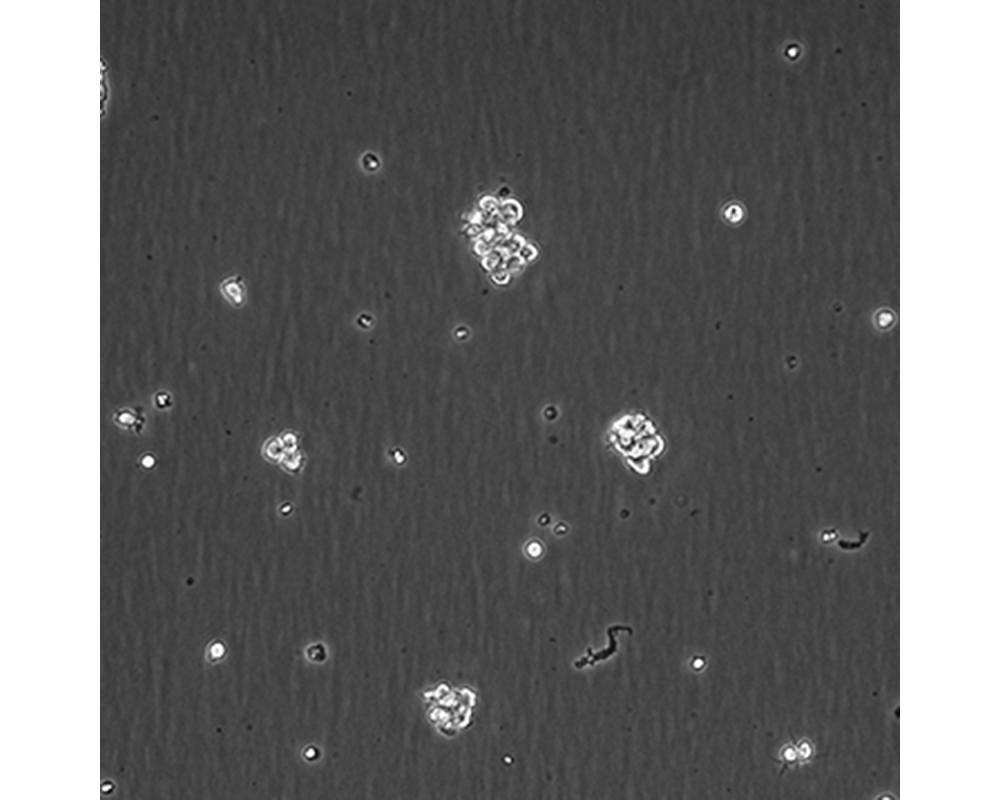

中文名稱 人間變性大細胞淋巴瘤細胞

組織來源 間變性大細胞淋巴瘤;胸腔積液轉移;女性

生長特性 懸浮

復蘇細胞步驟 將含有1mL細胞懸液的凍存管在37℃水浴中迅速搖晃解凍,加入4mL培養基混合均勻。在1000RPM條件下離心4分鐘,棄去上清液,補加1-2mL培養基后吹勻。然后將所有細胞懸液加入培養瓶中培養過夜(或將細胞懸液加入10cm皿中,加入約8ml培養基,培養過夜)。第二天換液并檢查細胞密度。